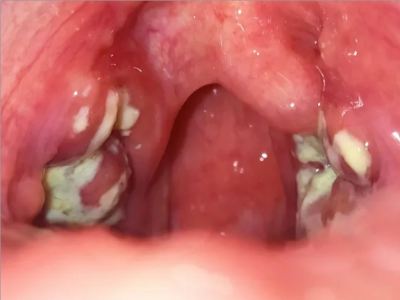

化脓性扁桃体炎喉咙两侧有白膜覆盖图

化脓性扁桃体炎咽部两侧扁桃体被黄白色假膜覆盖,形似白斑,假膜容易被擦去,假膜下的创面潮红,不易出血,伴有明显咽痛,吞咽时疼痛更加明显。